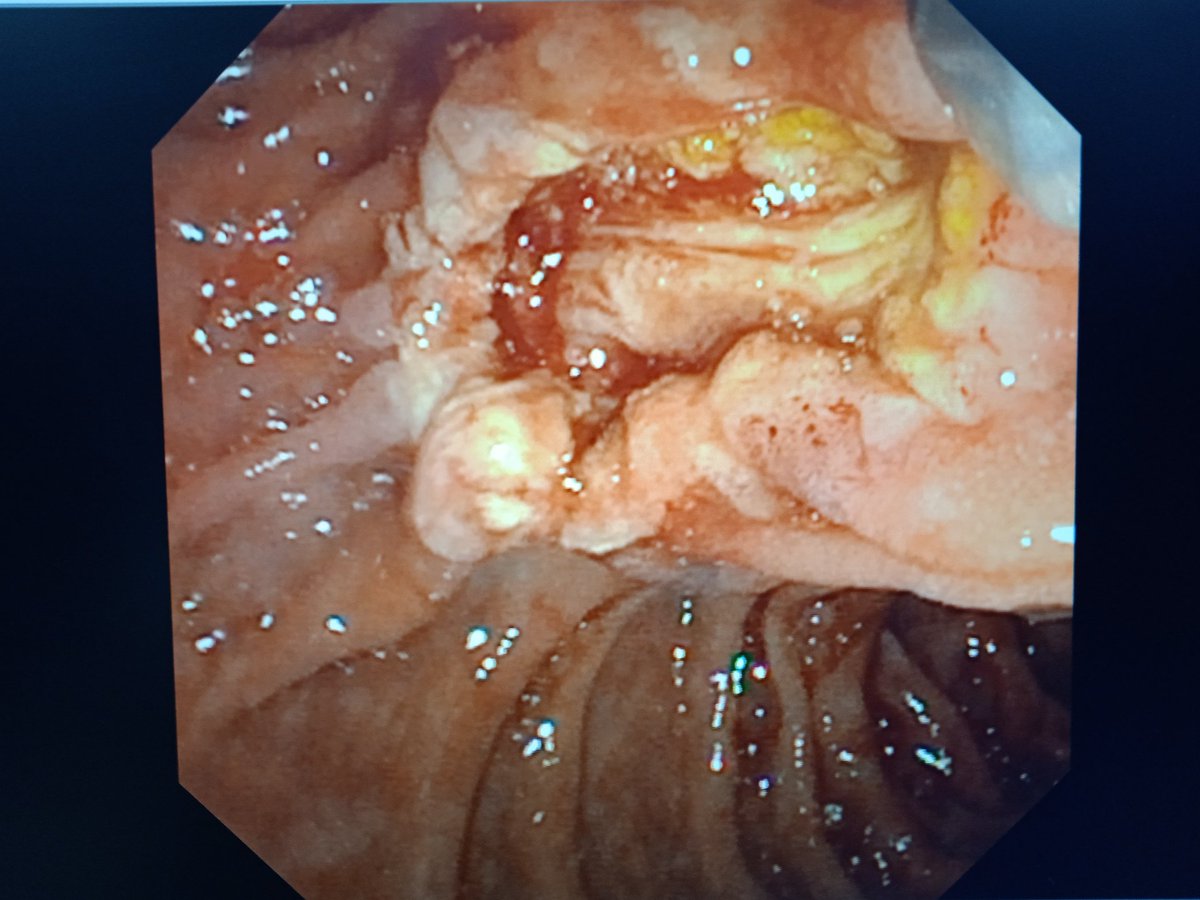

A case of ampullary NET Grade 1 on biopsy Eus/ct/mr suggest lesion limited to ampulla Ampullectomy done. The entire tumor was respected enbloc with intact surrounding capsule There was significant arterial bleeding- controlled with hemoclip application #AIIMSJodhpur